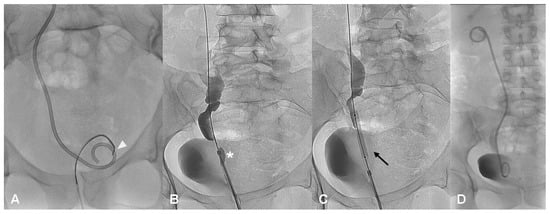

2.3.3. Ureteral Metallic Stenting

In one case of a ureterovaginal fistula, after keeping the DJ stent-nephrostomy system for a 3 month period, given the fistula persistence, an 8 mm × 80 mm metallic coated removable stent (Allium Medical Solutions, Caesarea, Israel; Figure 2A,B) was placed. Three months after the stent placement, because of fistula persistence, the patient underwent surgery.

In 3/15 (20.0%) patients, surgical treatment was needed: in one case because of the persistence of ureteral stenosis at 6 months, and in the other two cases due to ureter-vaginal fistula (Figure 2A,B).

Figure 2. (A,B)—A persistent fistula treated with ureteral stent. Left descending pyelographic study demonstrates a ureterovaginal fistula (black arrow) in the presence of a right DJ stent with opacification of both vaginal lumen (white arrow) and the bladder (asterisk) (A); removable metallic coated stent (white arrow head) is positioned without evidence of a fistula (B).